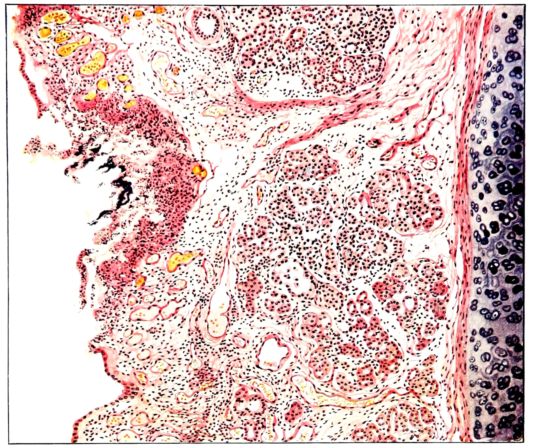

FIG. I. AUTOPSY NO. 99. ACUTE HEMORRHAGIC AND ULCERATIVE LARYNGOTRACHEITIS.

Early in the disease the congestion and the hemorrhages that have been described in the mucous membrane of the nasopharynx (14 and 94) are also conspicuous features in the lining of the trachea and bronchi (Fig. I). This membrane is swollen, turgid, red, and covered by a copious, mucous exudate which may be clear, but much more frequently is blood-stained or opaque and yellowish in color. The blood, variable in amount, may be fresh and red; and after the mucous exudate on the surface is removed, more intense red foci stand out on the congested base (47, 90, 157). Frequently, as the bronchi are approached, the red color of the mucosa becomes more intense and may have a garnet tinge. Membranes such as are encountered in the more usual necrotizing inflammatory processes, like diphtheria, have not occurred in the trachea and larger bronchi in this series (108, 128, 157).[3] The exudate peels off readily, and as indicated above, leaves a velvety red surface, 14dotted here and there with darker or more intensely red foci. Small ulcerations of the mucosa occur, but are inconspicuous (82, 156). As the finer ramifications of the bronchi are approached, the accumulation of the exudate in their lumina becomes more and more marked, and on cross section of the lung, they often stand out conspicuously on account of their increased size and projecting, seromucous, blood-stained content (101, 149, 162).